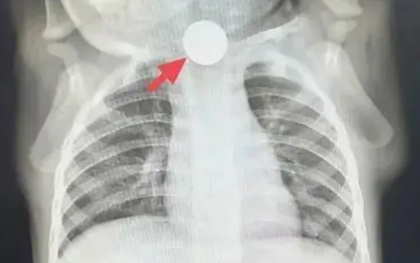

Một bé 1 tuổi bỗng nhiên thay đổi tính nết, chán ăn suốt một tuần! Sau khi được bác sĩ ở Thượng Hải thăm khám, nguyên nhân được phát hiện khiến bà nội nhận ra là sơ suất của mình.